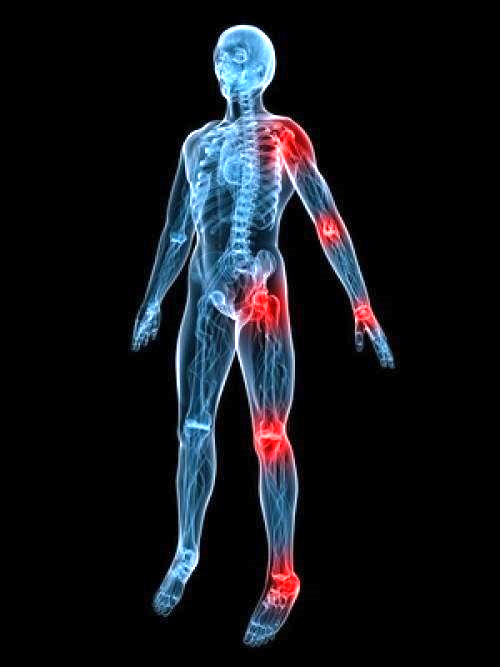

5. Správnym a pravidelným saunovaním v kvalitnej infrasaune dosiahnete aj zmiernenie bolesti kĺbov a ich stuhnutosti, zlepšuje stav artritídy.

6. Pravidelné saunovanie v kvalitnej infrasaune zmierňuje bolesti svalov, svalových kŕčov, burzitíd a napomáha k ich liečeniu.

8. Pravidelné využívaniekvalitnej infrasauny mápozitívny vplyv na celýkardiovaskulárny systém,podporuje krvný obeh.

9. Pravidelné saunovanie v kvalitnej infrasaune tiež pomáha pri liečbe vysokého tlaku

11. Správne saunovanie v kvalitnej infrasaune citeľne pomáha od bolestí chrbta či menštruačných bolestí.